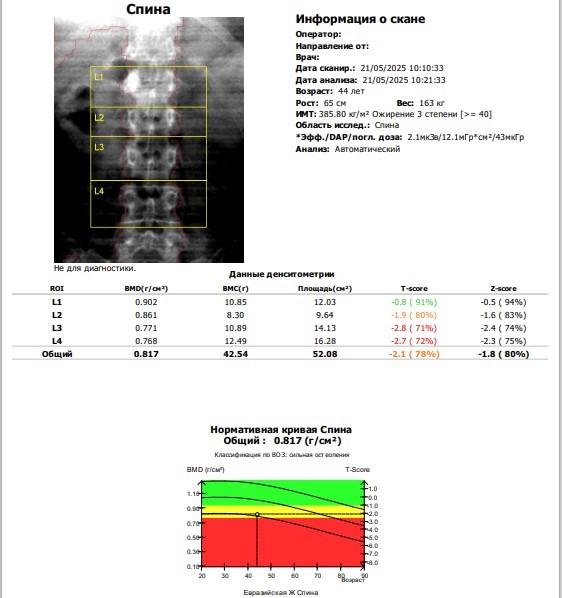

Для определения минеральной плотности костной ткани в клинике имени профессора Ю.Н. Касаткина РМАНПО применяется инновационный двуэнергетический рентгеновский остеоденситометр Stratos dR (DMS, Франция). Технология DXA (двухэнергетическая рентгеновская абсорбциометрия), т.н. «двойная энергия», позволяет достоверно оценить риск переломов и стадию остеопороза, а трехмерная технология (3D-DXA) — построить трёхмерные изображения костных структур. Денситометр оснащен 256 детекторами, системами лазерного наведения и автоматической калибровки, что позволяет в полной мере оценить текущее состояние различных отделов скелета (геометрию, толщину, минеральную плотность) с возможностью морфометрического анализа для выявления деформационных изменений.

Областью применения аппарата также могут быть как общая ортопедия, так и педиатрическая практика с возможностью исследования соответственно 8 и 4 областей с режимом «Все тело». Это инновационная программа для оценки тощей, костной и жировой массы, которая может быть полезна при выработке терапевтических подходов у пациентов с ожирением, анорексией, мышечной дистрофией, синдромом Кушинга, первичного и вторичного гипертиреоза и других заболеваний.